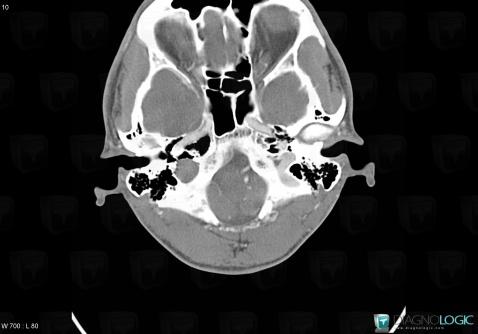

Schwannome, Foramen jugulaire, Autres nerfs craniens, Scanner

Voici les informations spécifiques à l'image clé ci dessus:

- Diagnostic Schwannome, Localisation(s) Foramen jugulaire, comportant les gammes Lésion du foramen jugulaireAutres nerfs craniens, comportant les gammes Lésion des nerfs craniens